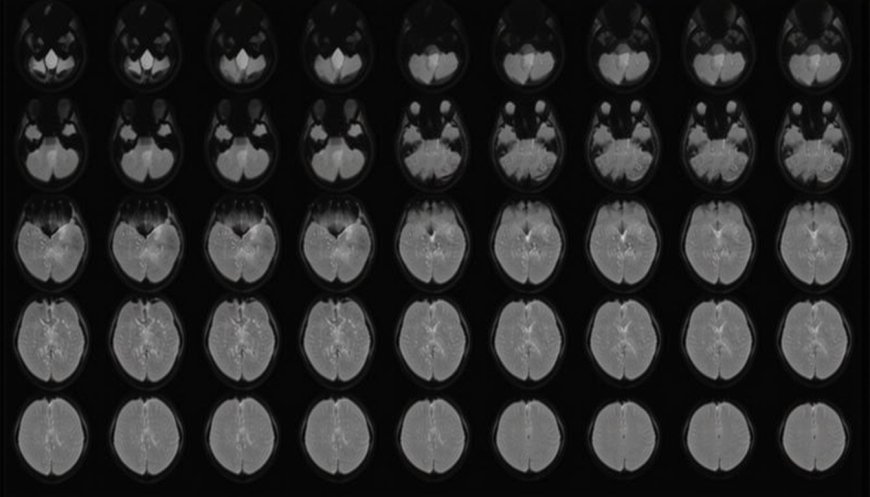

At NTT’s Communication Science Laboratories near Tokyo, Horikawa examined the brain activity of six Japanese-speaking adults, aged 22 to 37, as they watched a series of 2,180 silent video clips showcasing various scenes and actions.

Utilizing large language models, these AI systems transformed video captions into numerical sequences, which were then aligned with brain activity through simpler AI models called “decoders.”

These decoders were trained to correlate the brain scans with the numerical data, allowing the AI to interpret new brain activity from unseen videos, generating word sequences that matched the decoded information.